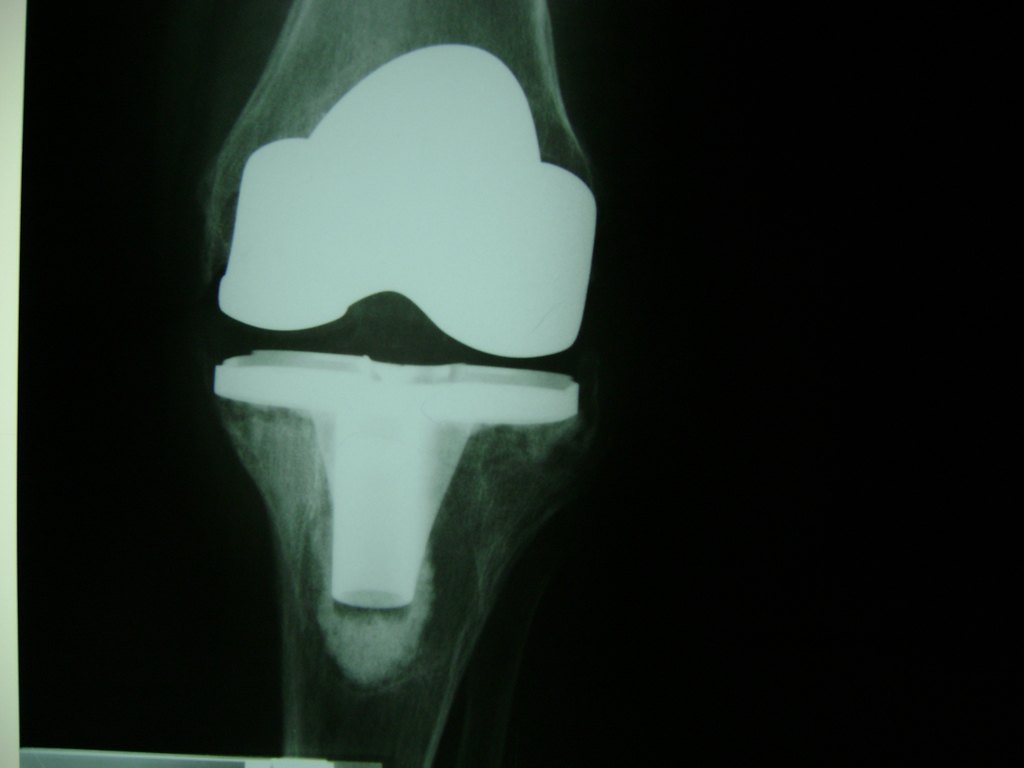

Cirugías de Peroné y Tibia

La artroscopia de rodilla es un cirugía en el cual la estructura interna de la articulación es examinada ya sea para realizar un diagnostico o para realizar un tratamiento, este procedimiento se realiza utilizando un instrumento parecido a un pequeño tubo llamado artroscopio.